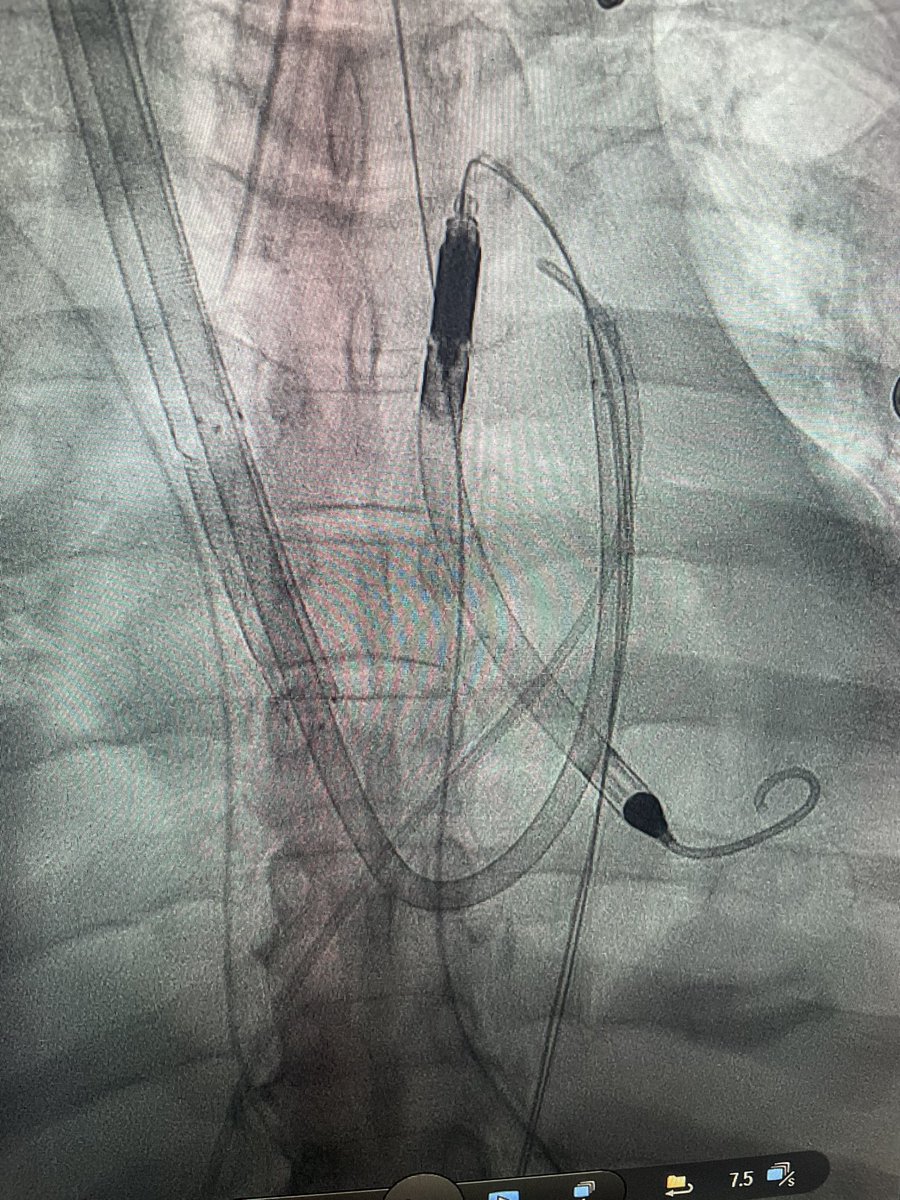

COVID myocarditis in a young obese patient with no other co morbid conditions. Rx with Transcaval 5.0 Impella and Protek. Escalated to ECPELLA. Stable but gaurded. Huge props to @AdamGreenbaumMD virtual support and @NavinKapur4 for curbside consults. Get vaccinated folks.

Dr Chirdeep Patel our MCS fellow did this case skin to skin. Surgical turndown Critical LM with CTO RCA. IVUS guided DK Crush with Impella in CKD patient. Total contrast 48cc. He used CO2 angio for large bore access and completion angio. Awesome to see such expertise.